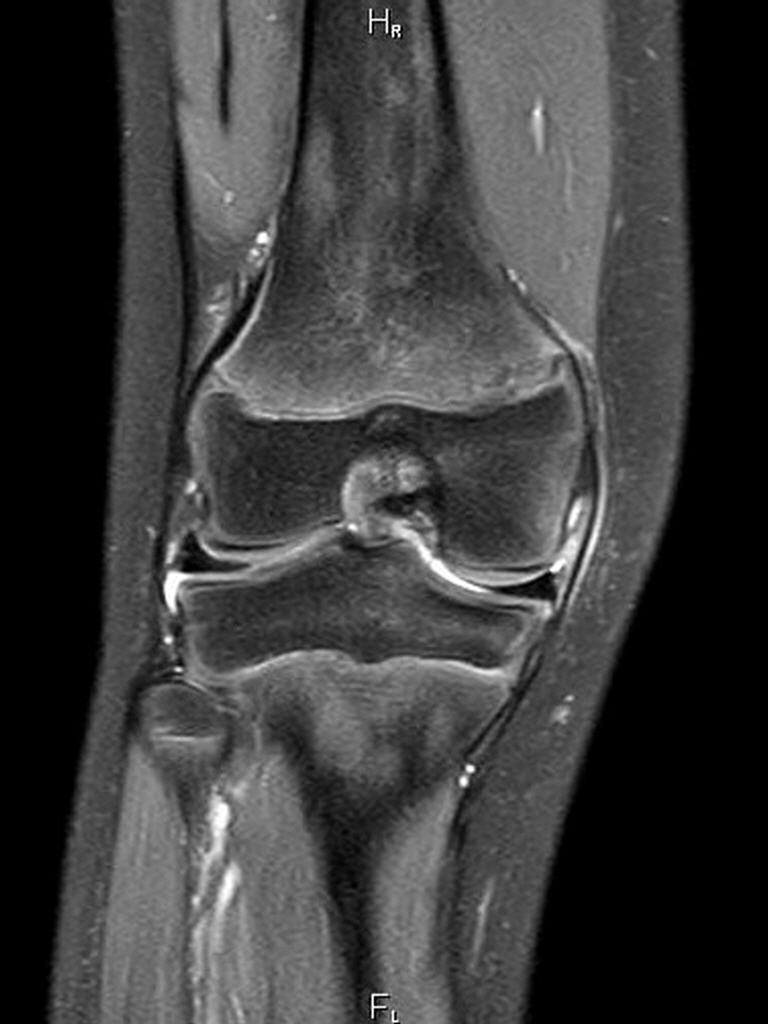

- Bildgebung aller Gelenke